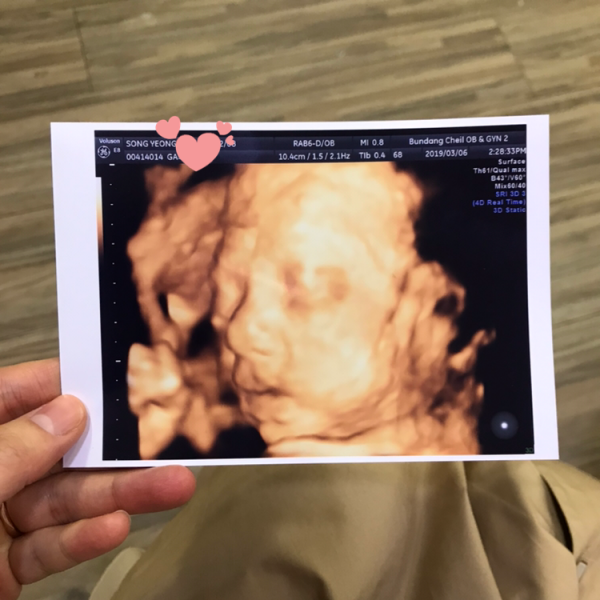

2019-04-29안녕하세요. 이현준님, 먼저 아내를 생각하는 마음이 가득 담겨진 편지라 더욱 더 따뜻함이 전해지는 것 같습니다. 더불어 예쁜 사진들과 이은성 과장님을 비롯한 많은 직원분들 한 분 한 분을 잊지 않고, 이렇게 정성스럽게 써주신 편지에 본원의 모든 직원들이 놀람과 감동을 크게 느켰습니다. 본원의 모든 선생님들이 친절한 것 같다는 말씀도 정말 감사드립니다.^^예쁘게 완성한 펠트만큼와 초음파 사진 속 현준님의 아이도 너무 사랑스럽고, 예쁩니다. 바쁘신 와중에 감사의 편지를 남겨주셔서 감사합니다. 전해주신 감사의 편지에 보답할 수 있도록 더욱 친절하고, 높은 의료 서비스로 발전하는 분당제일여성병원이 되겠습니다.